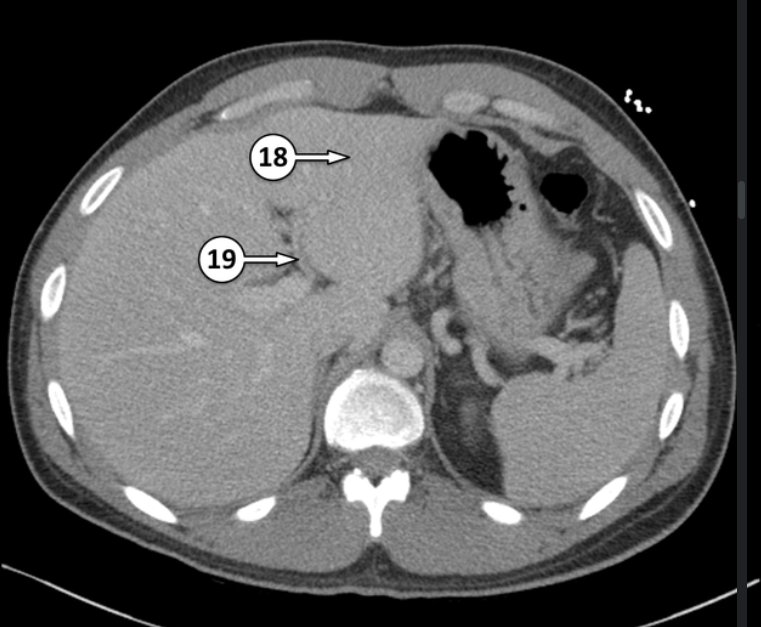

Please label 18 and 19

Segment III of the liver

Left Hepatic artery